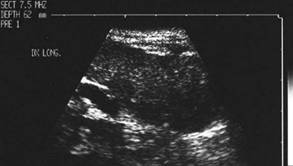

Femeie de 29 ani. Linfonodul in regiunea

laterocervicala dreapta ( 7x12x23mm, 1 cc) in neoplazie papilara a tiroidei. Structura

parenchimatoasa, neomogenea, cu margini

nete, cu absenta hilului.Examen citologic: metastaza de neoplazie papilara.